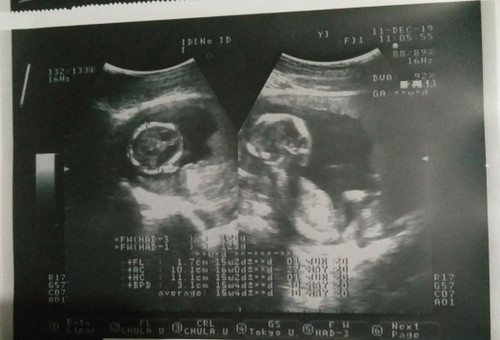

อวดภาพอัลตราซาวนด์ตอน15weekกันหน่อยจ้าาา

แม่ๆบ้านไหน15weekเห็นแบบนี้แล้วบ้างคะ เอามาอวดกันหน่อยเร็วววว บ้านนี้15weekหมอบอกว่าน้องให้ความร่วมมือดีมากจ้าา โชว์นิ้วมือให้หมอดูด้วย แต่ท่านอนหนูจะคล้ายแม่ไปไหนลูก แม่นอนท่าไหนหนูก็นอนท่าเดียวกับแม่ ไม่ต้องบอกเลยคะว่าลูกใคร นอนก็ยังทำท่าเหมือนแม่อีก น่ารักอะไรขนาดนี้คร้าาา